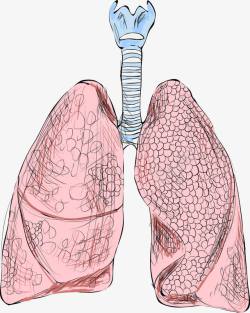

人体肺部结构解剖